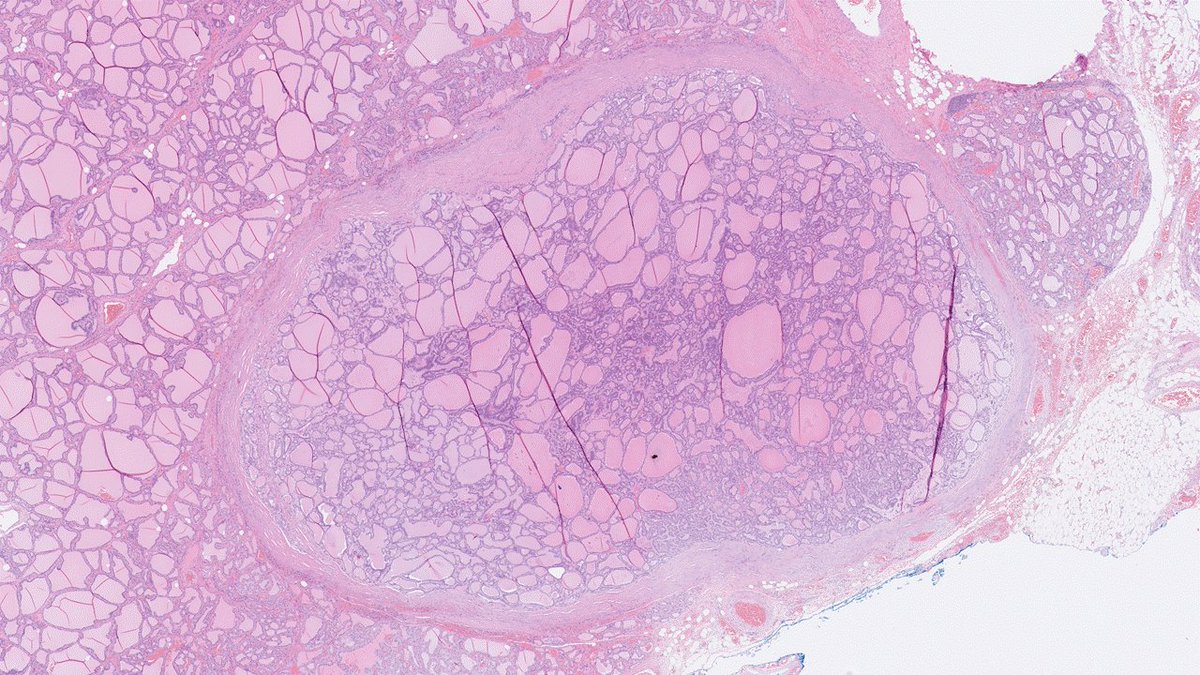

34-year-old female patient with Graves' disease. No prior FNAC. Planned for thyroidectomy, but surgery was limited to the left lobe due to loss of nerve signals. 6 mm nodule evident during grossing. Encapsulated and well demarcated, macro- to microfollicular pattern: